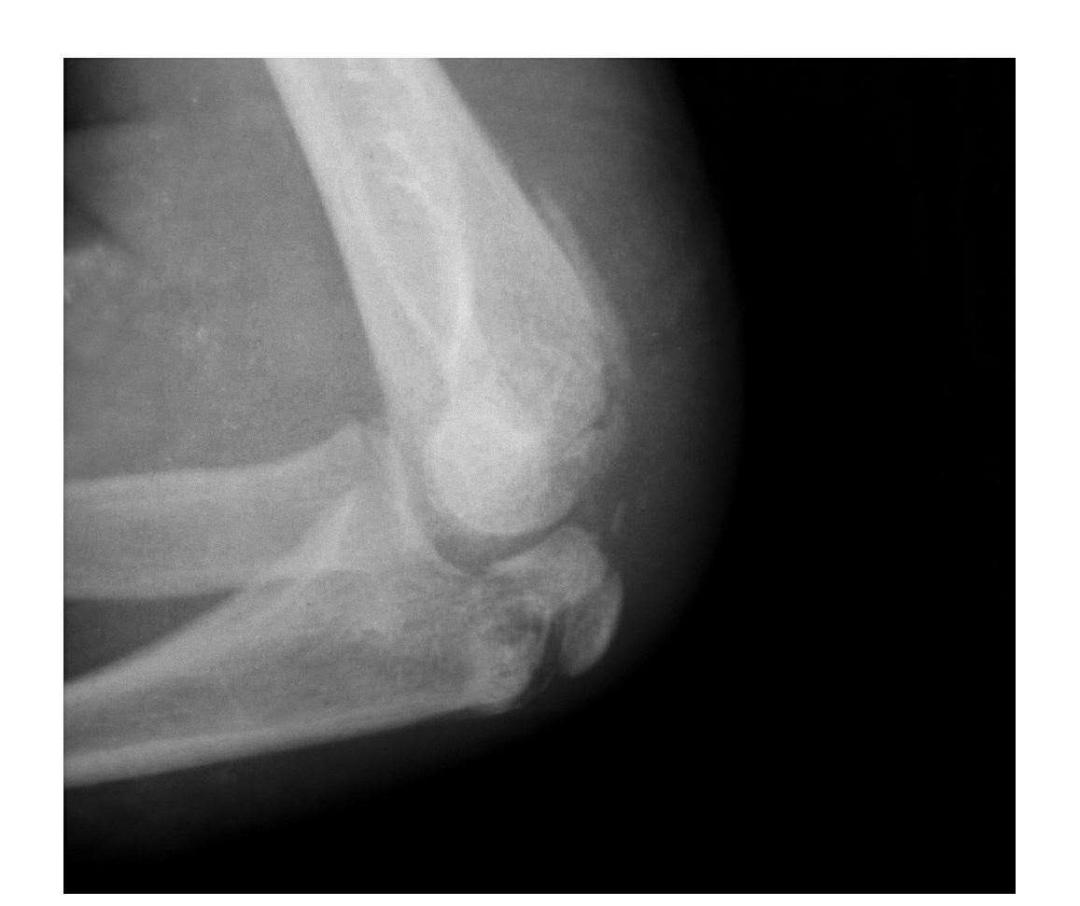

肱骨小头冠状面骨折

(一)完全骨折

本病亦称哈-斯(Hahn-Steinthal)型骨折

例1:肱骨小头基底部呈冠状面骨折,骨折块呈半球状向肘前上方移位。